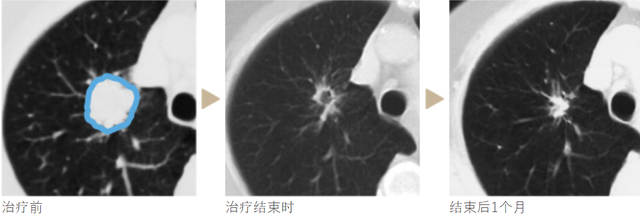

典型案例治疗进度图: